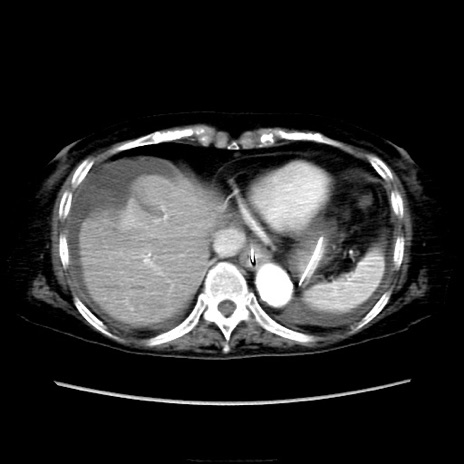

他院CT

横断像

【症例】90歳代女性

【主訴】腹痛・嘔吐

【身体所見】腹部:中央に激痛あり、圧痛あり、反跳痛不明

【データ】WBC 17100、CRP 18.82